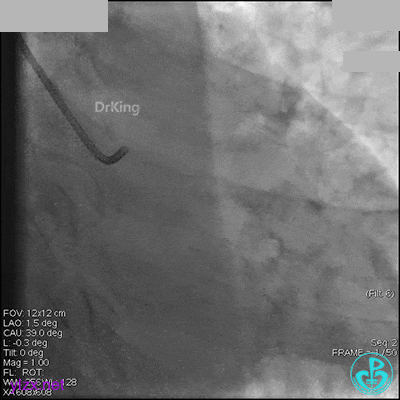

冠脉造影

入院次日冠脉造影显示粗大左主干末端中度狭窄,前降支开口严重狭窄,回旋支与前降支角度大,弥漫性长病变,严重狭窄,粗大右冠脉近中段弥漫性中重度狭窄。由于病变复杂,造影结束后先下台,择期再行介入治疗。